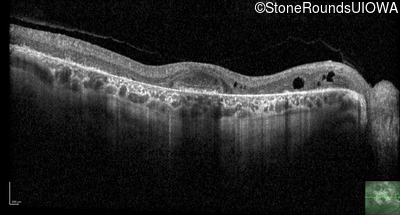

Optical Coherence Tomography - Left - 20/25 -2

Exemplar / OCT Stack